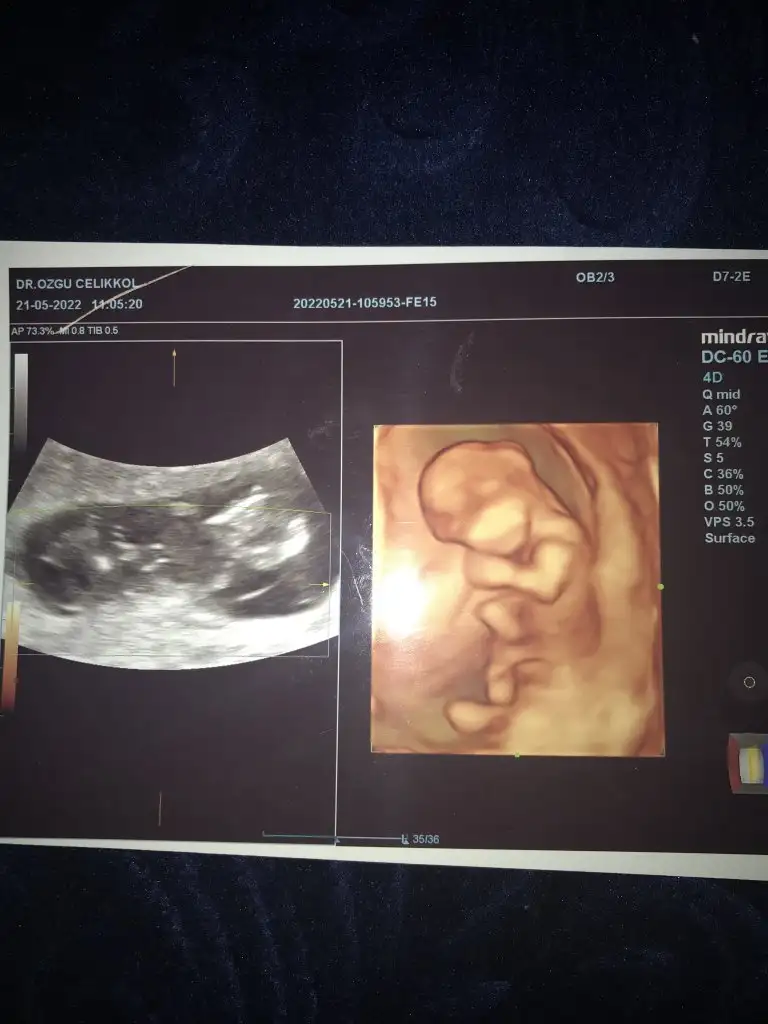

Bana da bi tahmin yapar mısınız?![]()

Kız görünüyor13. Hatfta cinsiyet tahmini yapabirmisiniz